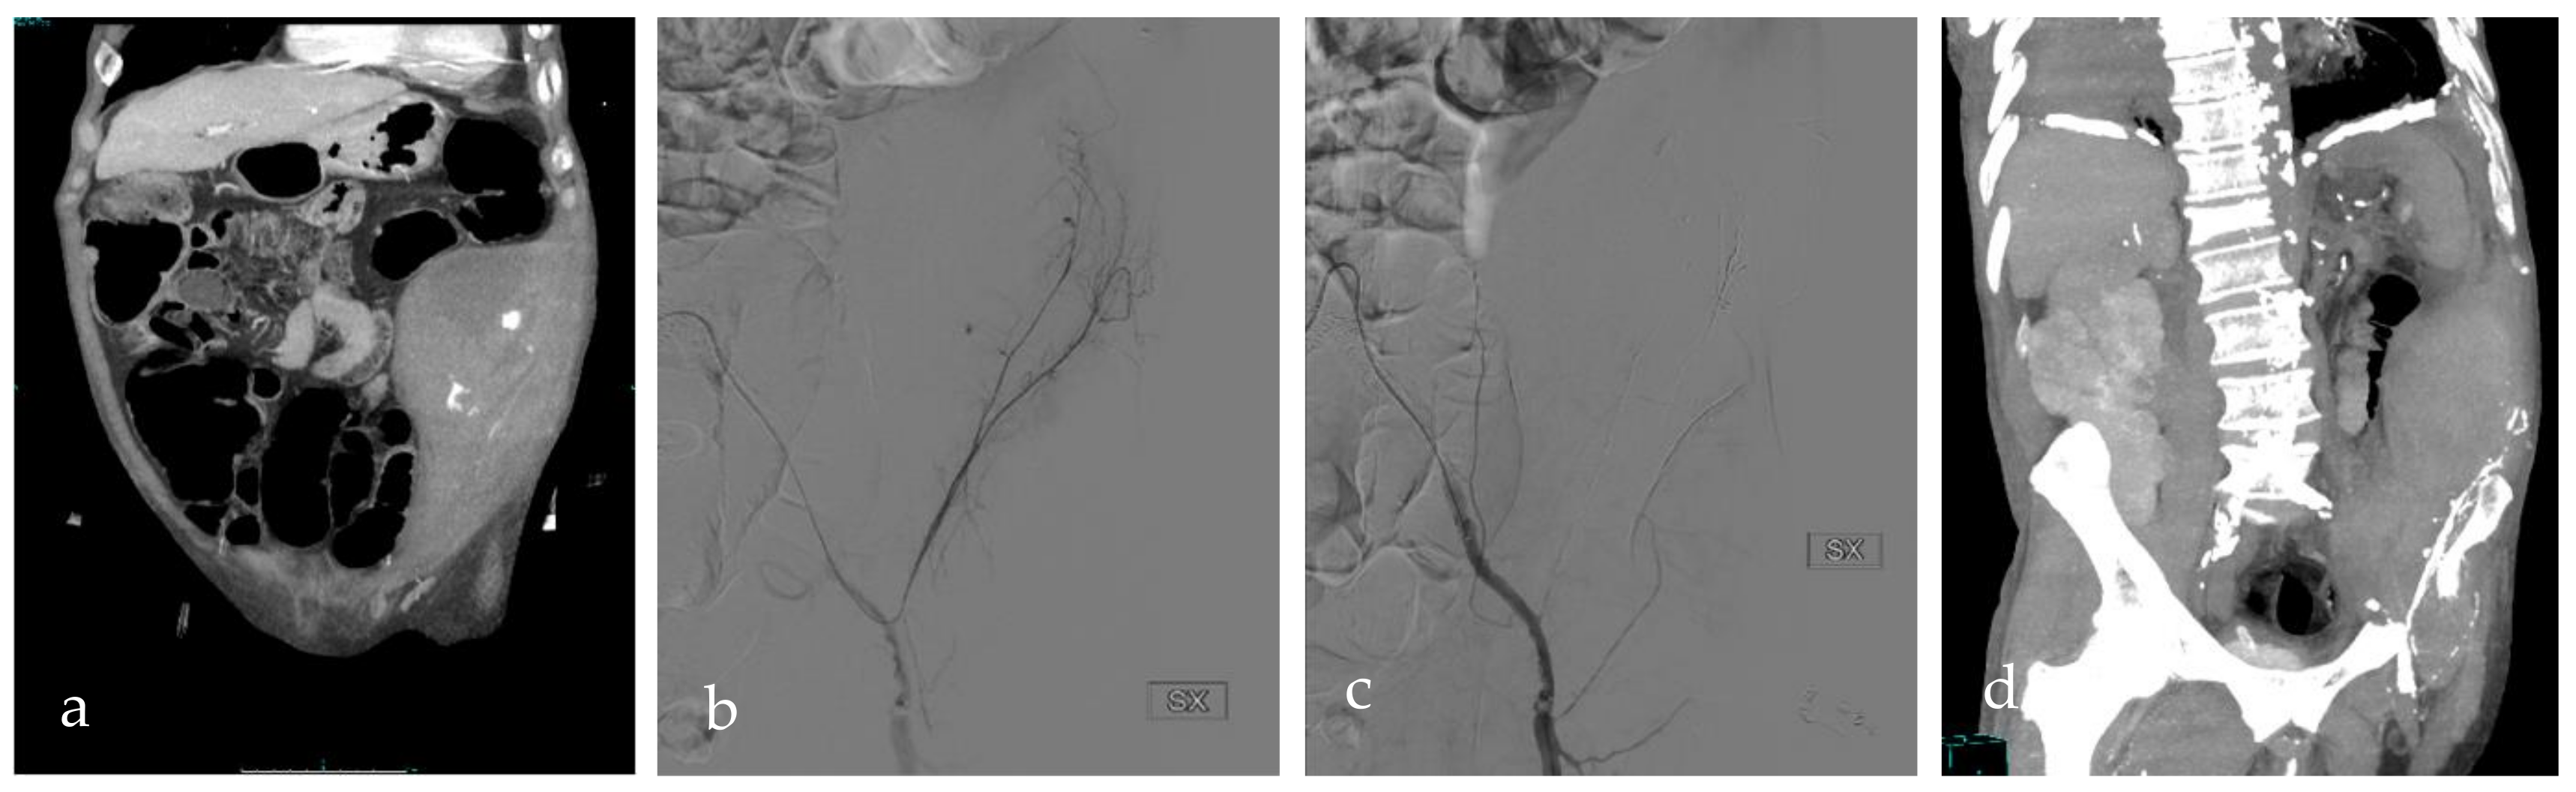

Figure 3.

RG, an 81-year-old man under therapy with acetylsalicylic acid and rivaroxaban, showed a loss of 2 points of hemoglobin. (a) CT scan documented an intramuscular hematoma with active bleeding in the left iliac and transverse muscles. (b) DSA confirmed multiple active bleedings from the deep circumflex artery’s branches. (c) DSA after glue injection, which showed the bleeding interruption. (d) CT scan after the procedure demonstrated hematoma reduction and initial resorption. SX = left.